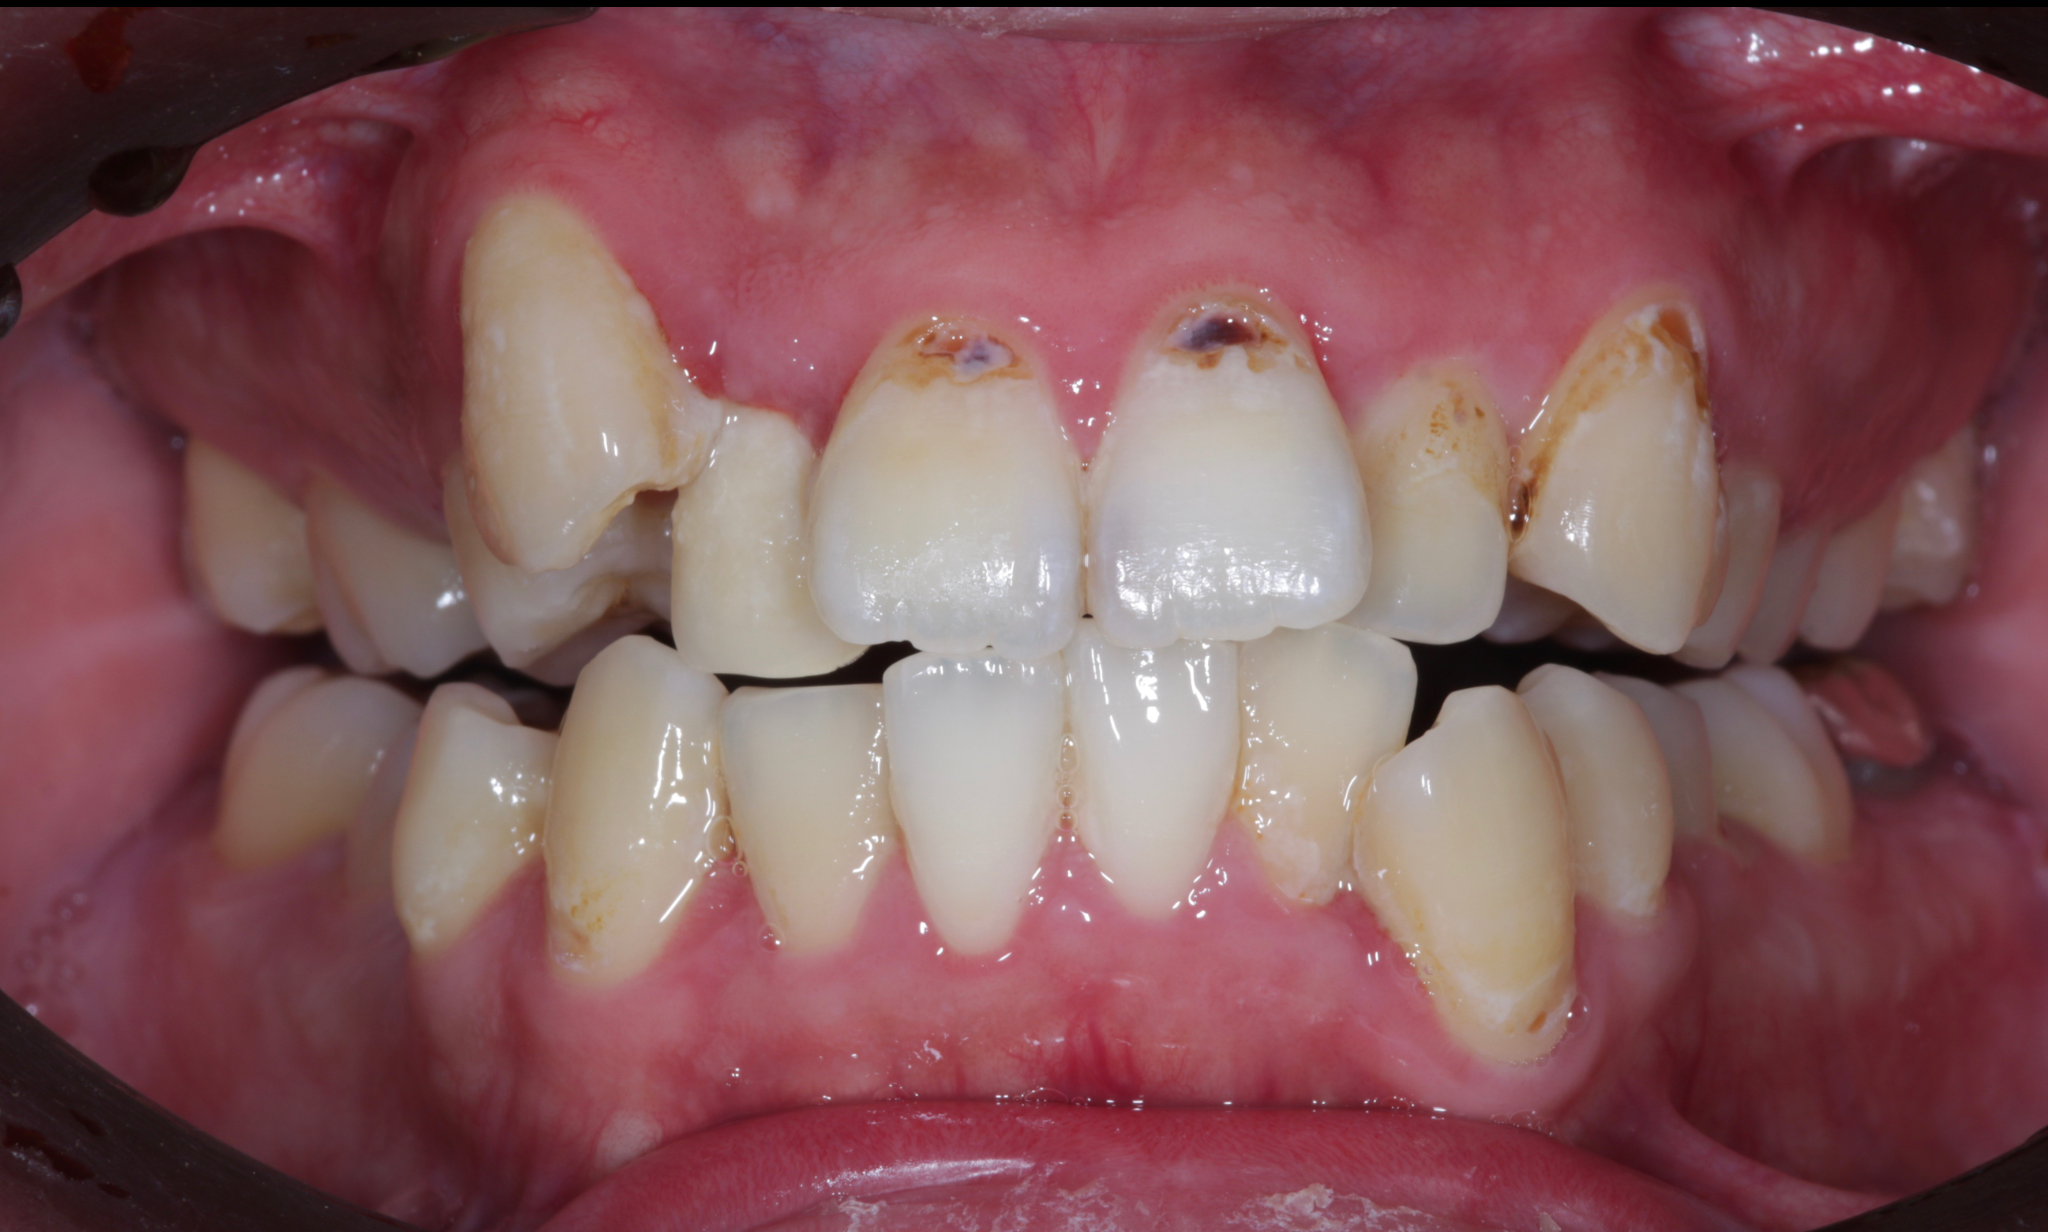

症例1:重度の叢生を矯正治療で改善した症例

術前の状態